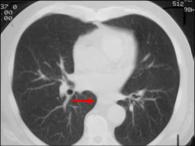

Azygo-esophageal recess